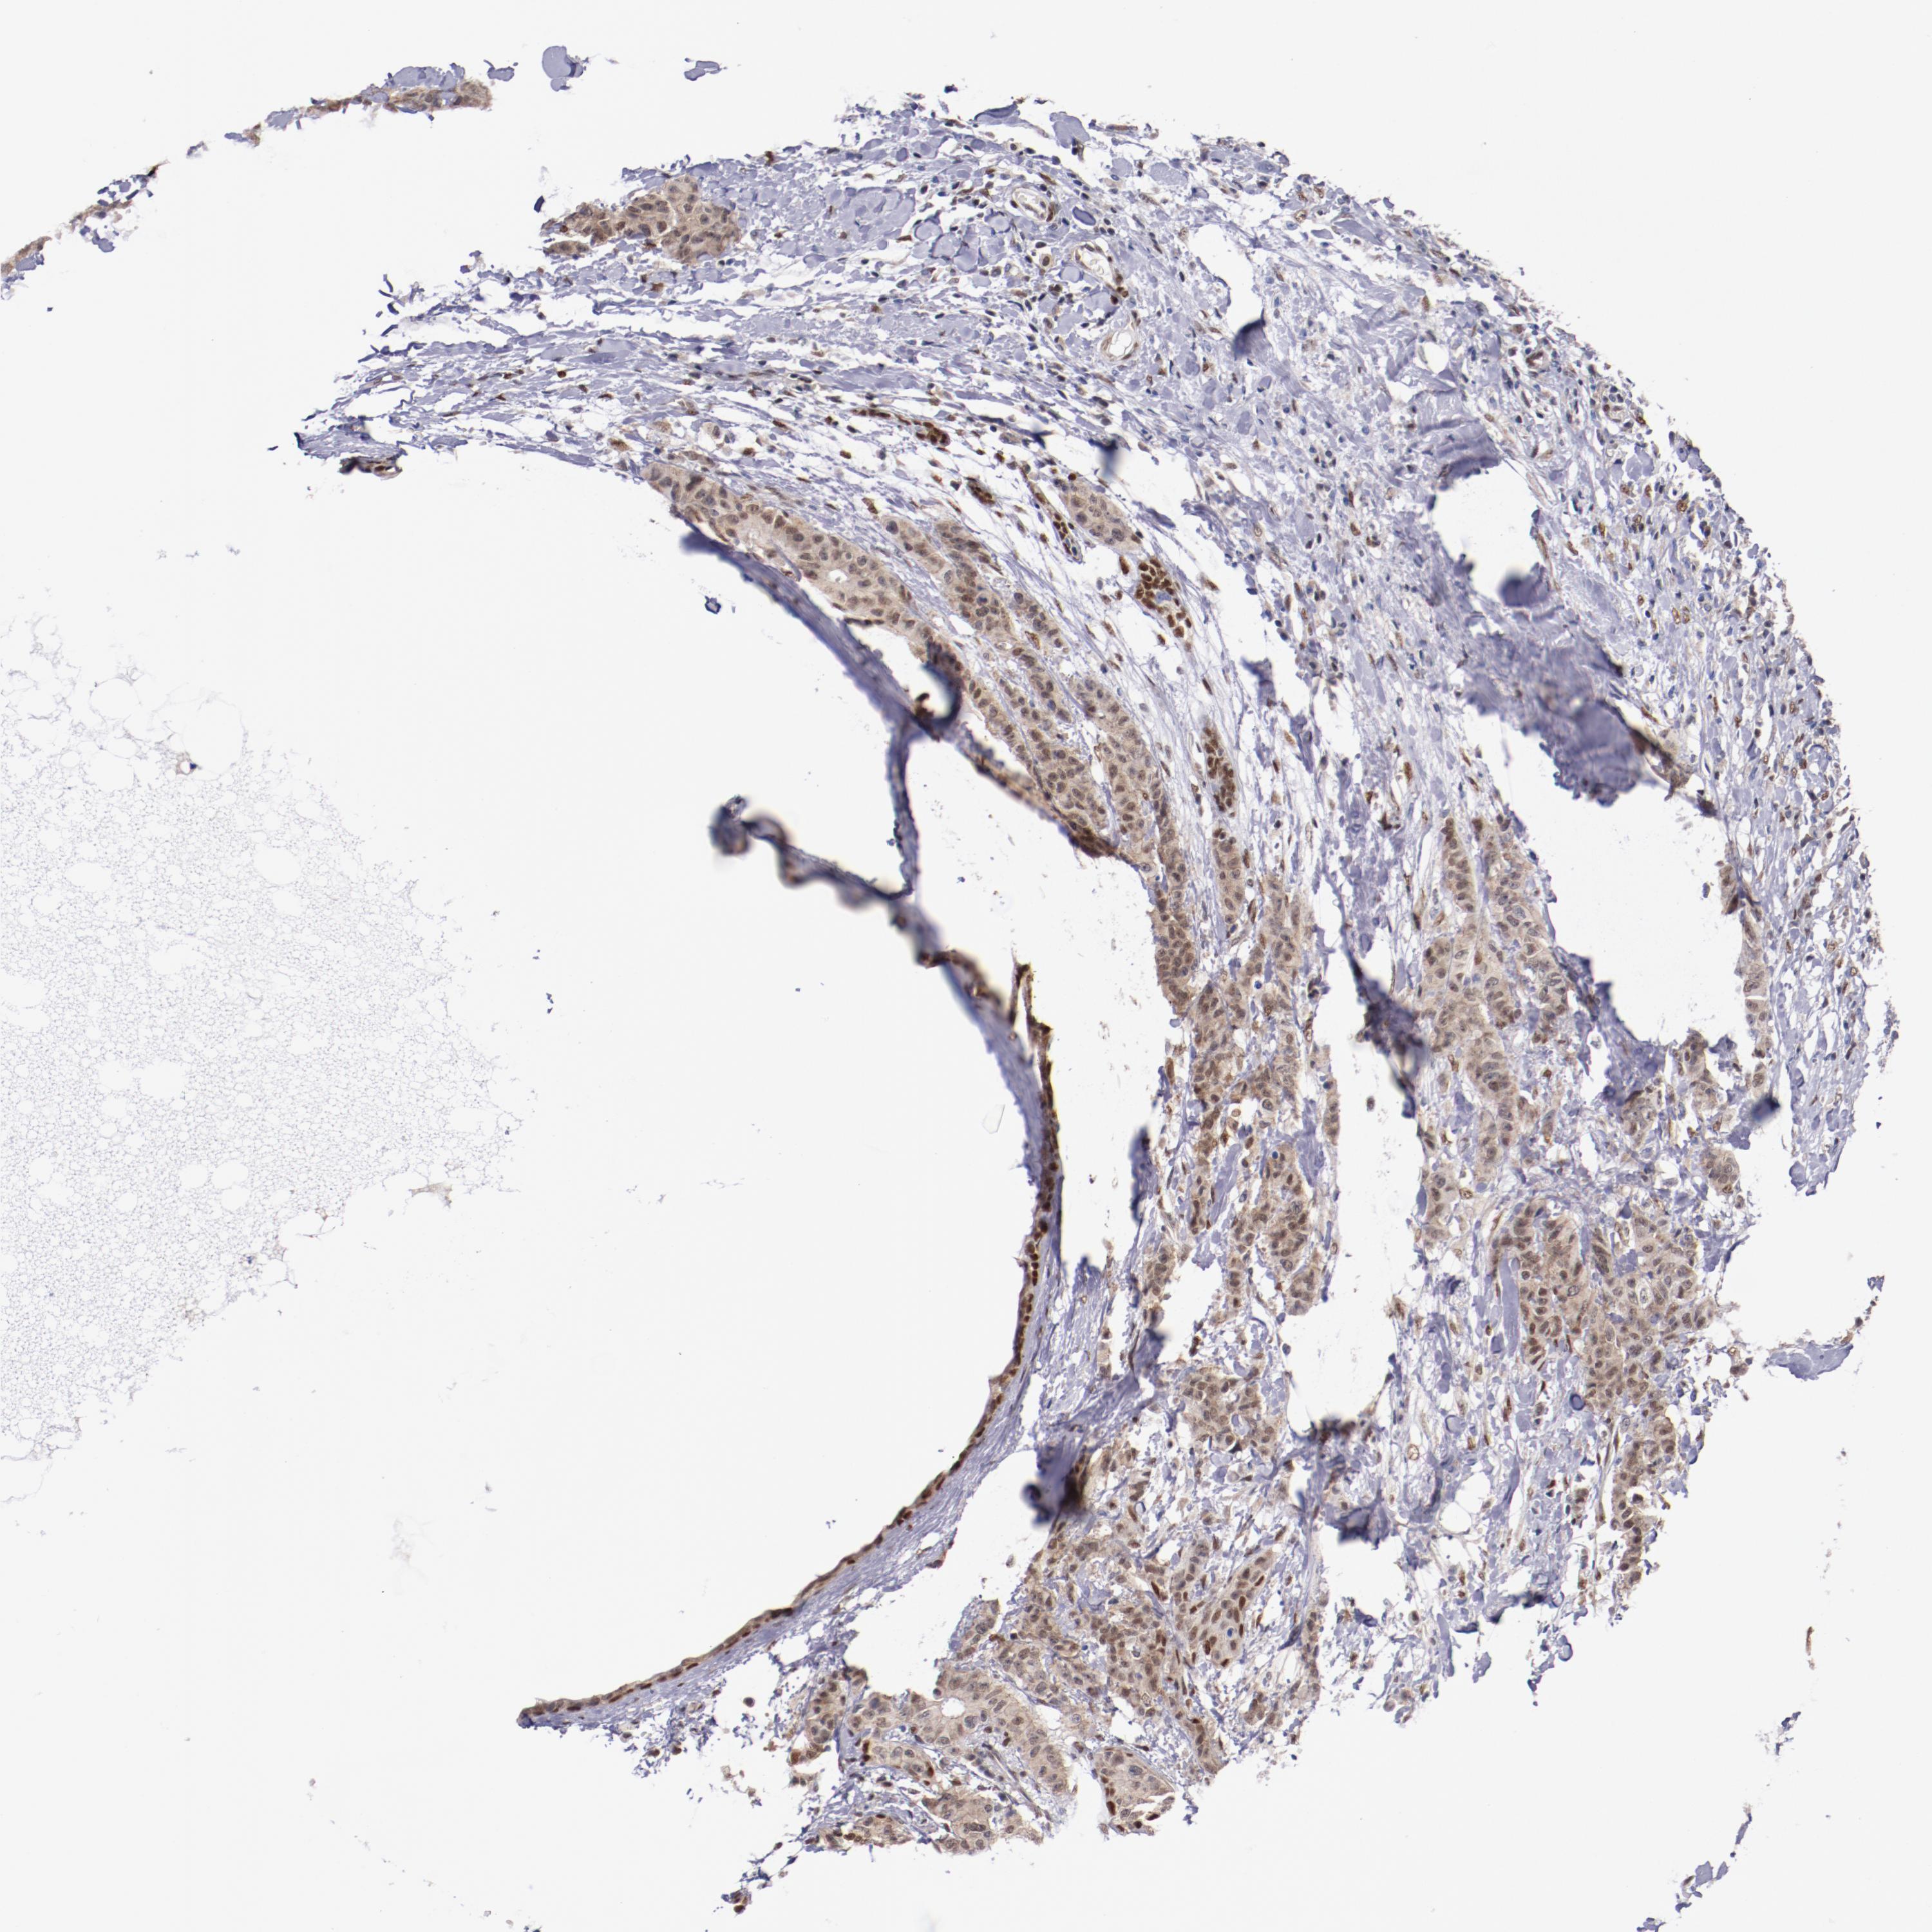

CANCER BREAST CANCER Show tissue menu

BRCA TCGA BRCA VALIDATION PROTEIN EXPRESSION